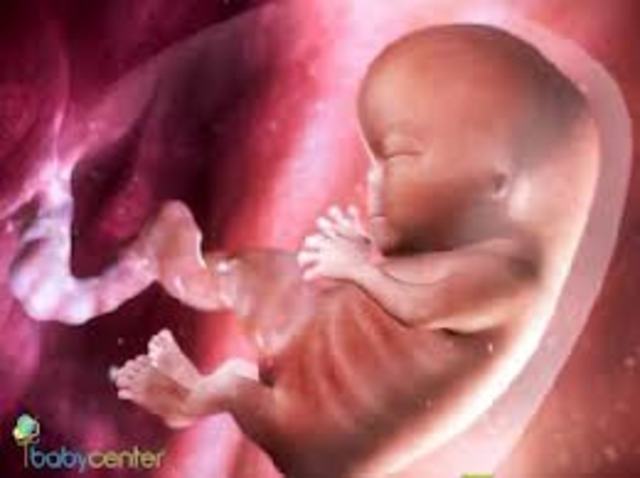

Fetal Develpoement:

-Size: About 1/4 inch (6mm) long as month begins

-Face, eyes, ears, and limbs take shape.

-Bones begin to form.